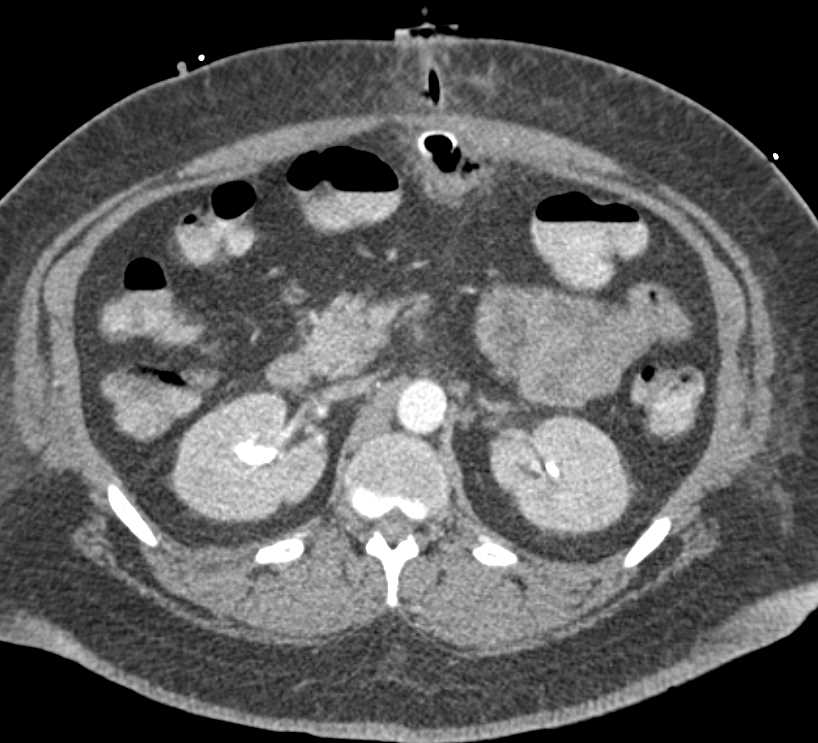

Gastric Varices and Large Collaterals with Cinematic Rendering